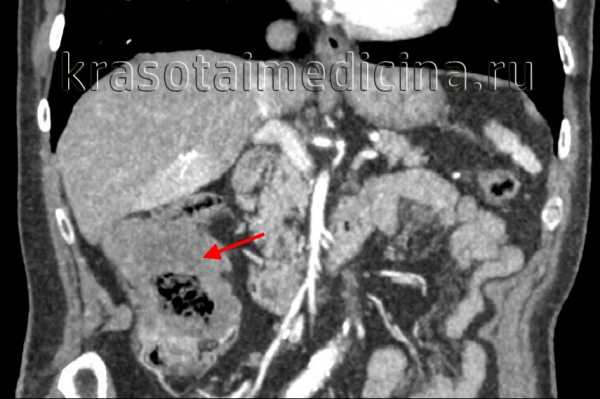

КТ ОБП. Опухоль поперечной ободочной кишки, прорастающая в переднюю брюшную стенку. (фото Вишняков В.Н.)